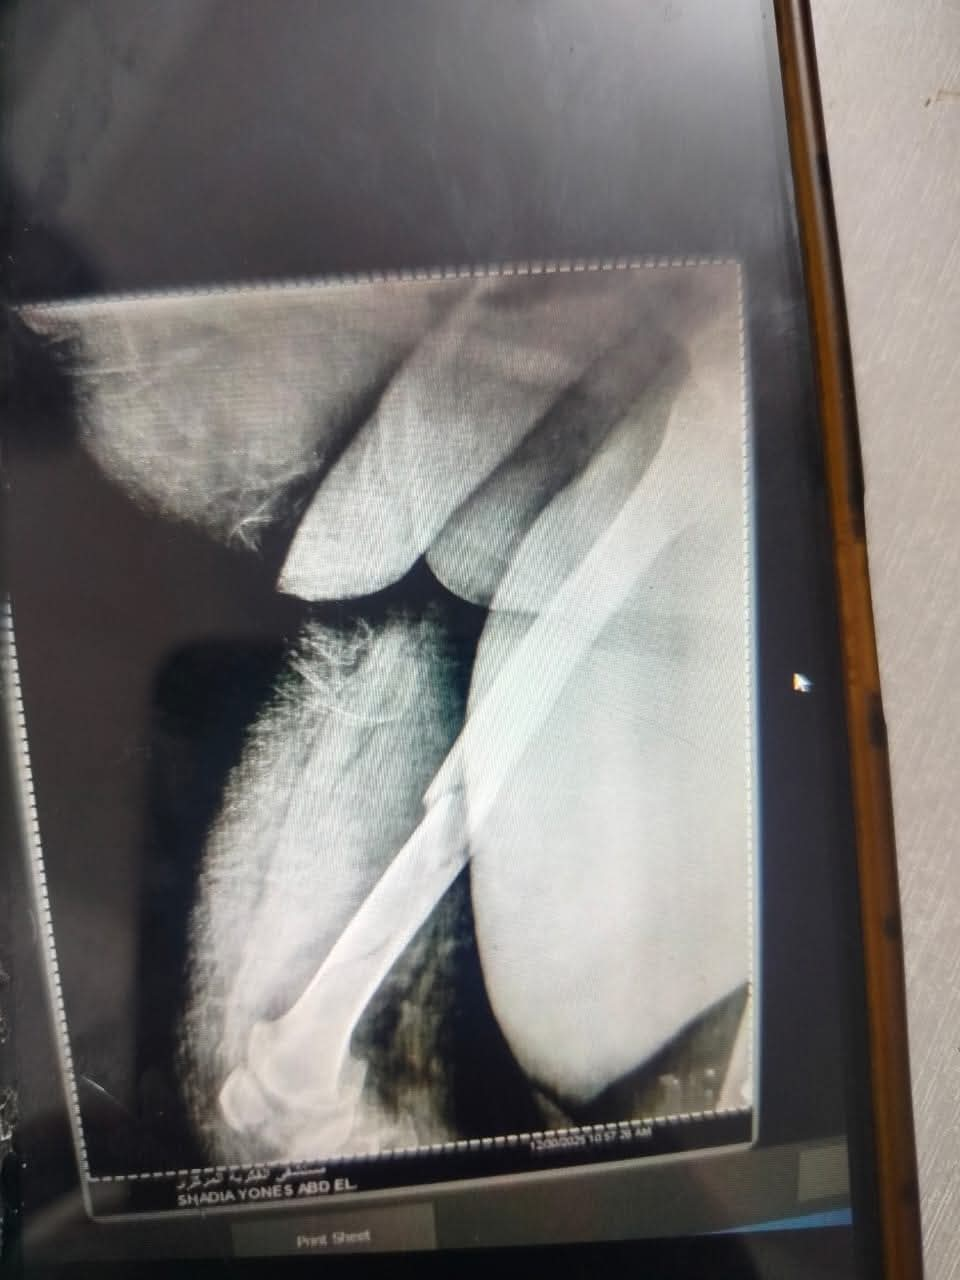

في إنجاز طبي جديد يعكس مدى التطور والكفاءة بمستشفى الفكرية المركزي بأبوقرقاص، نجح الفريق الطبي بقسم العظام في إجراء جراحة دقيقة ومعقدة لسيدة تبلغ من العمر 53 عاماً، وتزن 150 كيلو جرام، كانت تعاني من كسر بعظمة الفخذ، في حالة طبية استثنائية نظراً لإصابتها بمرض السكري وتحديات الوزن الزائد.

في خطوة طبية متقدمة، تم التدخل الجراحي وتثبيت الكسر باستخدام "المسمار النخاعي الارتجاعي" عن طريق مفصل الركبة، وهي تقنية حديثة تتطلب مهارة فائقة، خاصة في التعامل مع حالات الأوزان المرتفعة، مما يسمح للمريضة بالتعافي السريع والعودة للحركة في وقت قياسي.